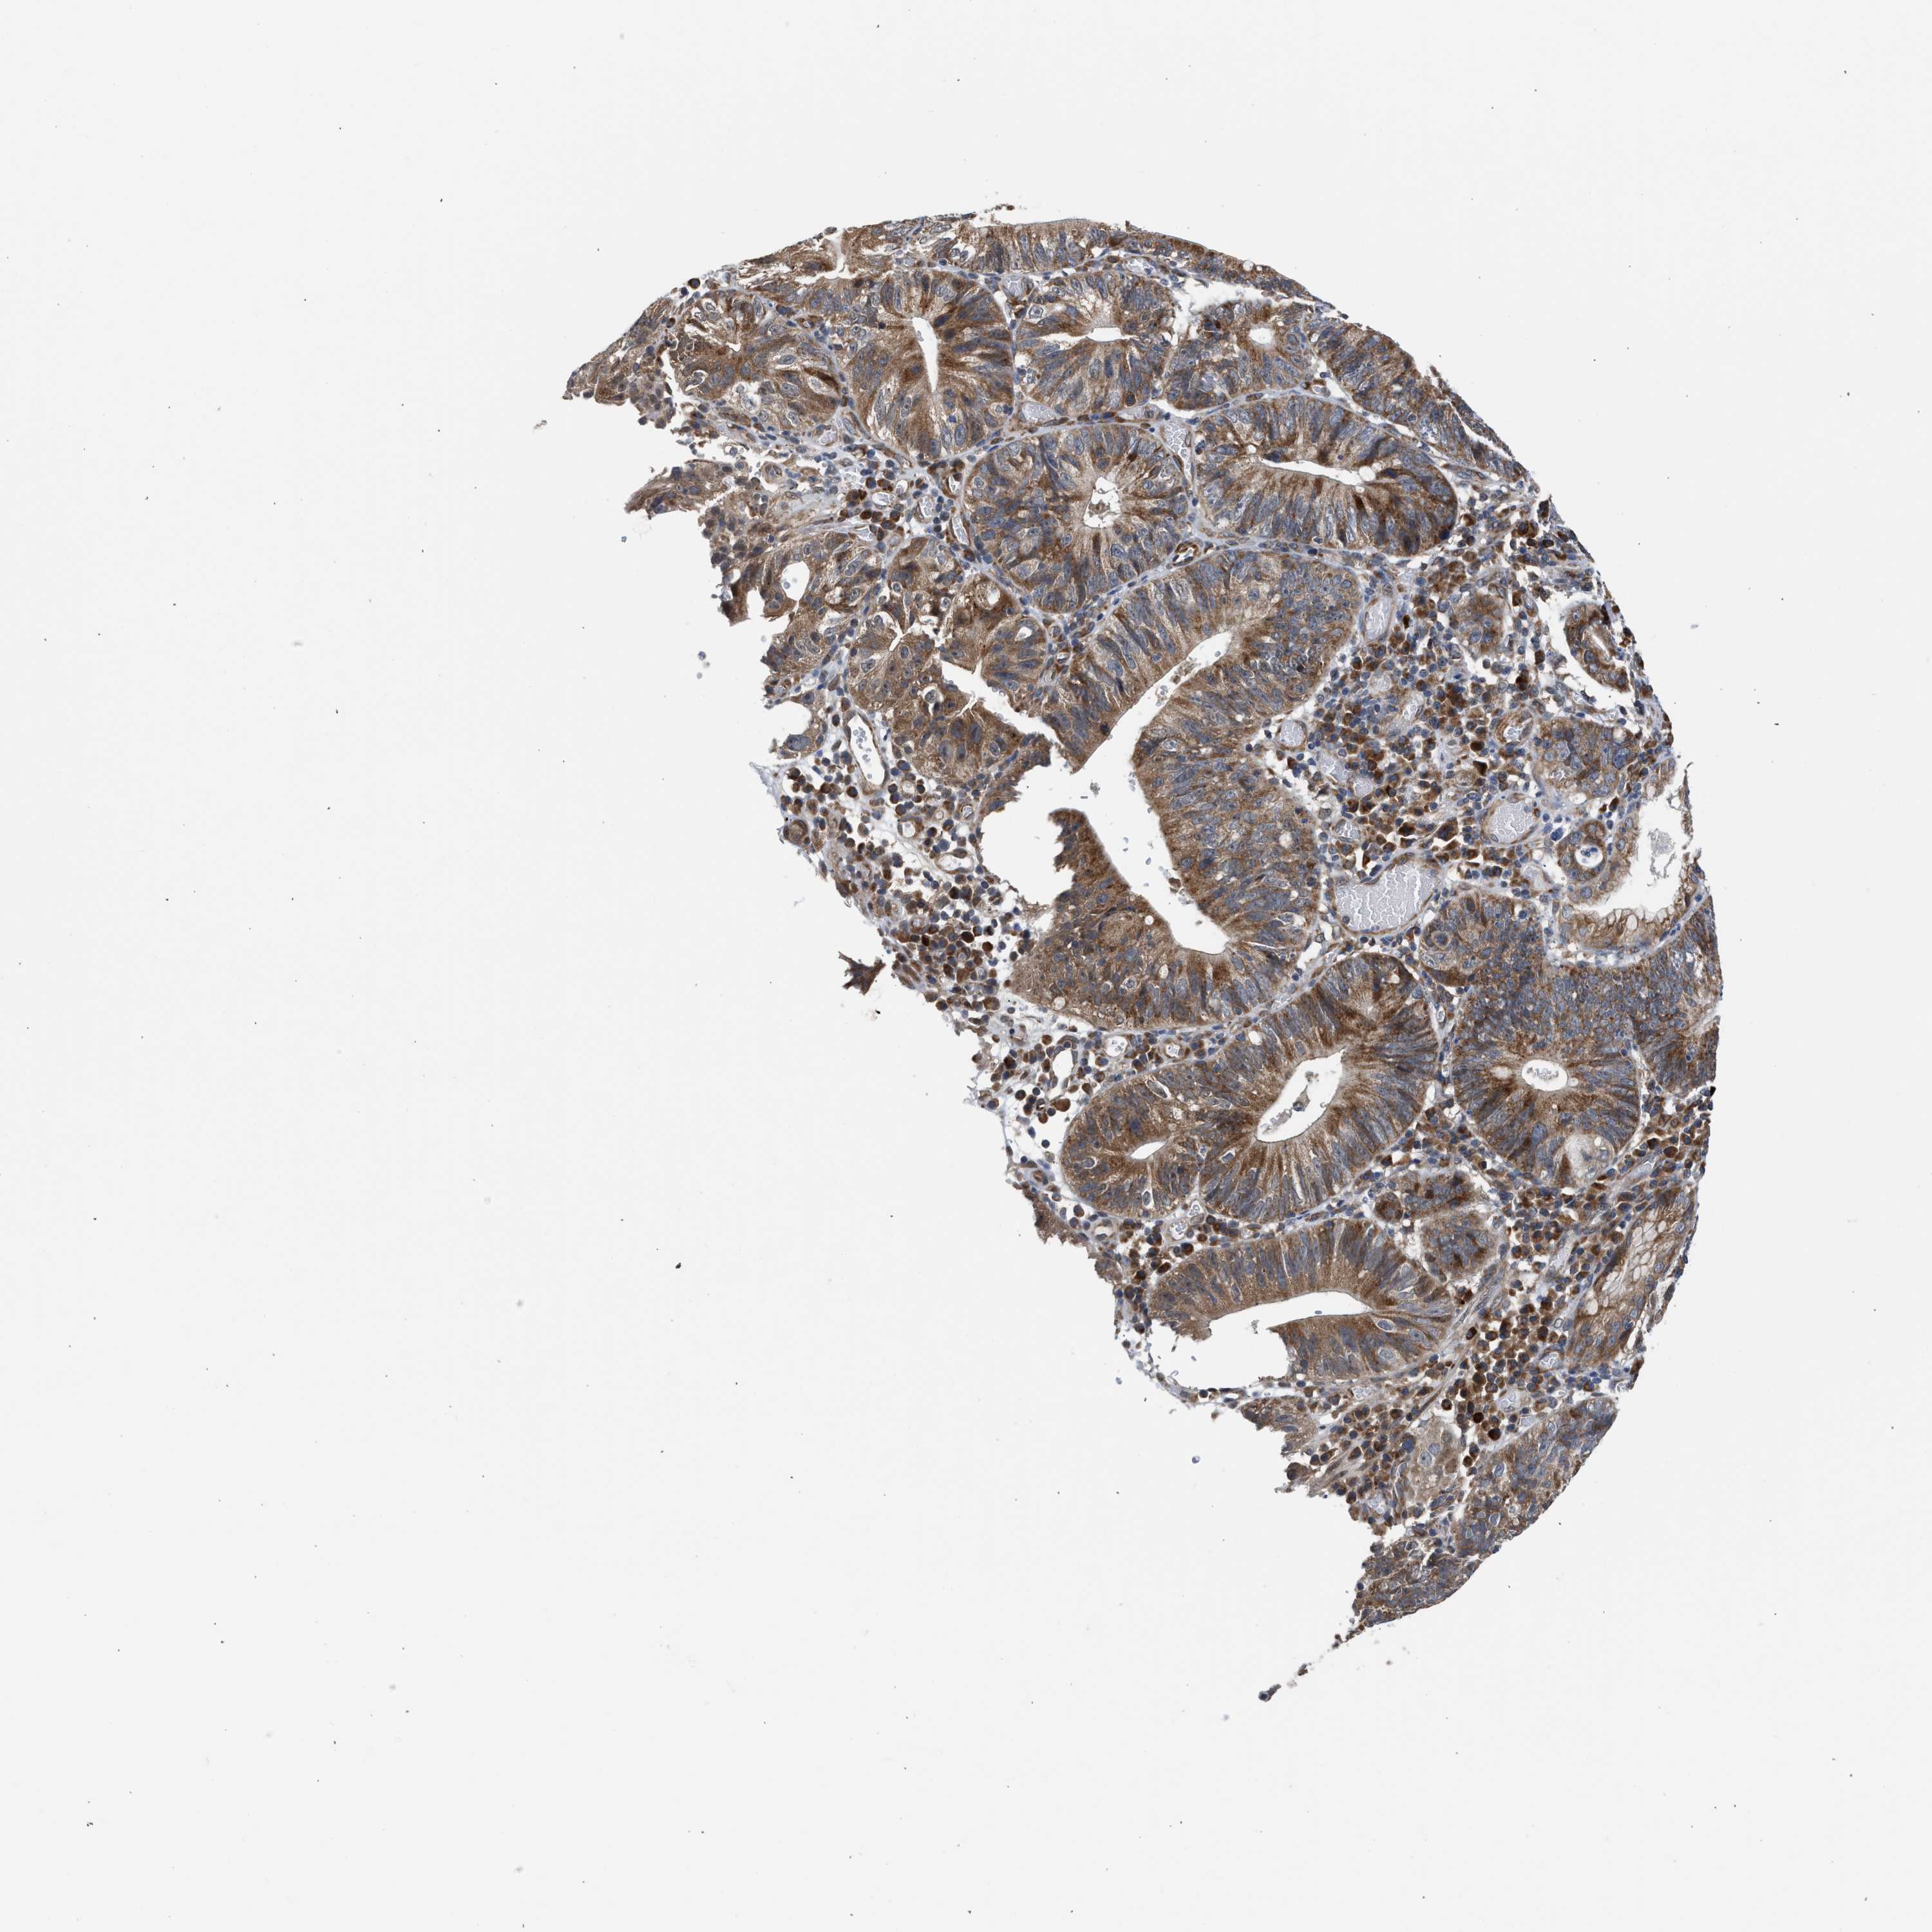

STOMACH CANCER - Protein expressioni

A mouse-over function shows sample information and annotation data. Click on an image to view it in a full screen mode. Samples can be filtered based on level of antibody staining by selecting one or several of the following categories: high, medium, low and not detected. The assay and annotation is described here.

Note that samples used for immunohistochemistry by the Human Protein Atlas do not correspond to samples in the TCGA dataset.

Antibody stainingi

Antibody staining in the annotated cell types in the current human tissue is reported as not detected, low, medium, or high, based on conventional immunohistochemistry profiling in selected tissues. This score is based on the combination of the staining intensity and fraction of stained cells.

Each image is clickable and will lead to virtual microscopy that enables deeper exploration of all samples and also displays staining intensity scores, fraction scores and subcellular localization as well as patient and tissue information for each sample.

Antibody HPA023202

Antibody CAB017030

Staining

High

Medium

Low

Not detected

Intensity

Strong

Moderate

Weak

Negative

Quantity

>75%

75%-25%

<25%

None

Location

Nuclear

Cytoplasmic/membranous

Cytoplasmic/membranous,nuclear

Adenocarcinoma, NOS

Adenocarcinoma, High grade